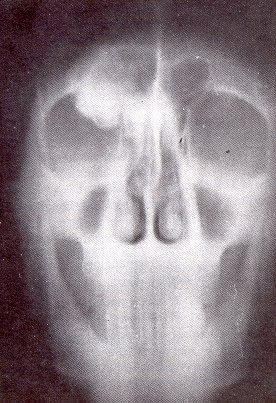

1. Osteoma (cráneo)

• Localización: Frontal, senos nasales, bóveda craneana, paladar, hueso esponjoso o cortical

• Radiología:

Zona totalmente osteocondensada